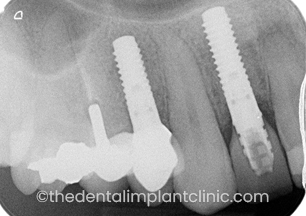

Jane was knocked over by a car aged 11 and her two front teeth experienced a severe trauma and subsequently died. For almost three decades, Jane had received extensive dental work including crowns and bridges. These continued to fail and she also experienced a number of abscesses as a result of the problems with her two front teeth.

‘I was referred by my dentist to The Dental Implant Clinic as he felt that implants were the only solution to my ongoing problems with my two front teeth. For my initial consultation, I was very impressed and the before and after pictures of previous patient cases really convinced me to take the dental implant route.’

The treatment

Because of the huge amount of dental work Jane had previously received, she had become quite concerned about the implant treatment. The Dental Implant Clinic explained that all of the major work could be carried out under sedation and also suggested that she have a friend accompany her to offer support prior to being sedated. Following the initial consultation, the two teeth were carefully removed and replaced by two implants. During the period that the implants were healing, a denture was fitted.